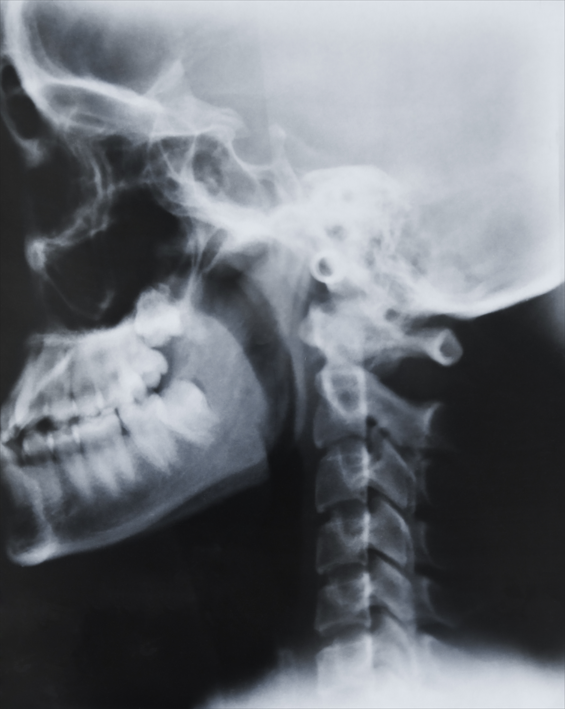

목디스크 (경추 추간판 탈출증)

목디스크는 경추의 디스크가 탈출하거나 손상되어 신경을 압박함으로써 목과 상체에 통증과 기능 장애를 유발하는 상태입니다.

목디스크는 신경 압박으로 인해 팔과 손에 지속적인 통증과 감각 이상을 유발할 수 있으며, 심각한 경우 운동 기능 장애나 만성적인 통증으로 이어질 수 있습니다.

적절한 치료가 이루어지지 않으면 일상 생활에 큰 영향을 미치고 장기적인 신경 손상을 초래할 수 있습니다.